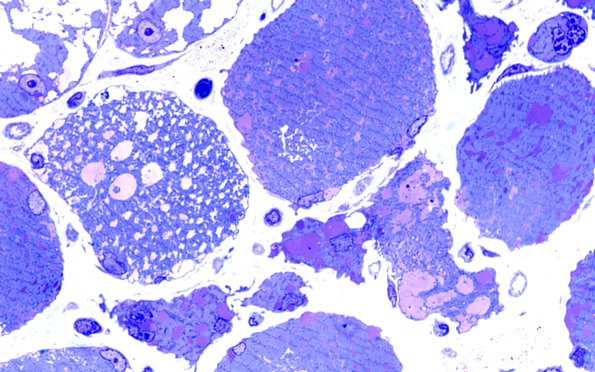

Pompe Disease

5C7 Muscle (Case 5) Plastic 100X 5

Several fibers are particularly vacuolated with variable content. (Plastic sections)